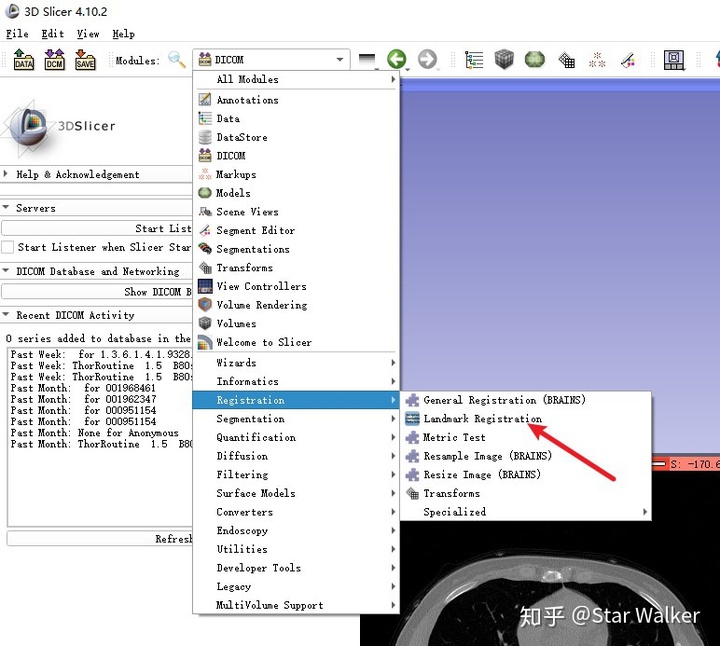

配准问题,其实属于医学图像处理中经常遇到的一类”钉子“,3D Slicer中也相应提供了多把锤子,也就是缺省集成了多种配准工具。大家可以看一眼下图。

启动Landmark Registration

加载好数据,改好名称之后,就可与启动Landmark Registration模块,开始配准了。启动的操作路径如下图。